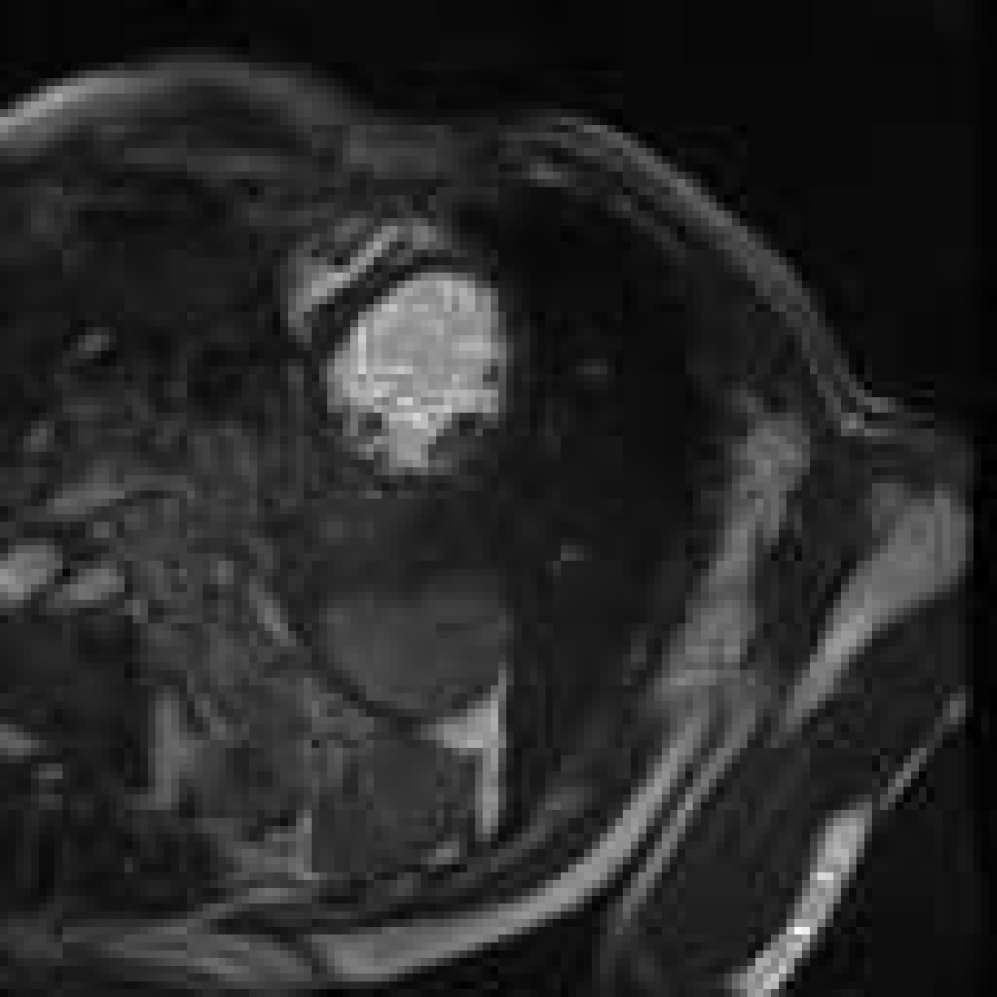

Figure 4: Image synthesis using various τ\tau and diffusion range NN with fixed D=4D=4. Since τ\tau controls the step size of guidance, a very small τ\tau results in no guidance.

Figure 5: Controlling structural consistency by extremal settings of DD and τ\tau. All images are synthesised using the same reference (indicated with a yellow arrow in Fig.  4). From left to right: (D=16D=16, τ=1\tau=1), (D=32D=32, τ=1\tau=1), (D=1D=1, τ=18\tau=18), and (D=1D=1, τ=24\tau=24). Large DD induces semantic drift; high τ\tau leads to more preservation of the reference anatomy.

Synthetic cardiac MR images (Fig. 4 and Fig. 4) closely resembled their respective reference image with good reconstruction on the three important regions of interest (LV, RV, MYO). With different refinement scale for image adaptation, the cardiac MR images had different level of reconstruction, highlighting a controllable trade-off between introducing novel synthetic structures and preserving reference anatomy (Fig. 5). Visual assessment revealed occasional white artifacts in the background of the generated images, likely caused by residual noise retained during the reverse process. Nevertheless, the overall anatomical structures remained well-preserved, even in the presence of a limited dataset. While diffusion models are traditionally considered data-hungry, our results suggest that structural fidelity can be maintained with constrained data availability.